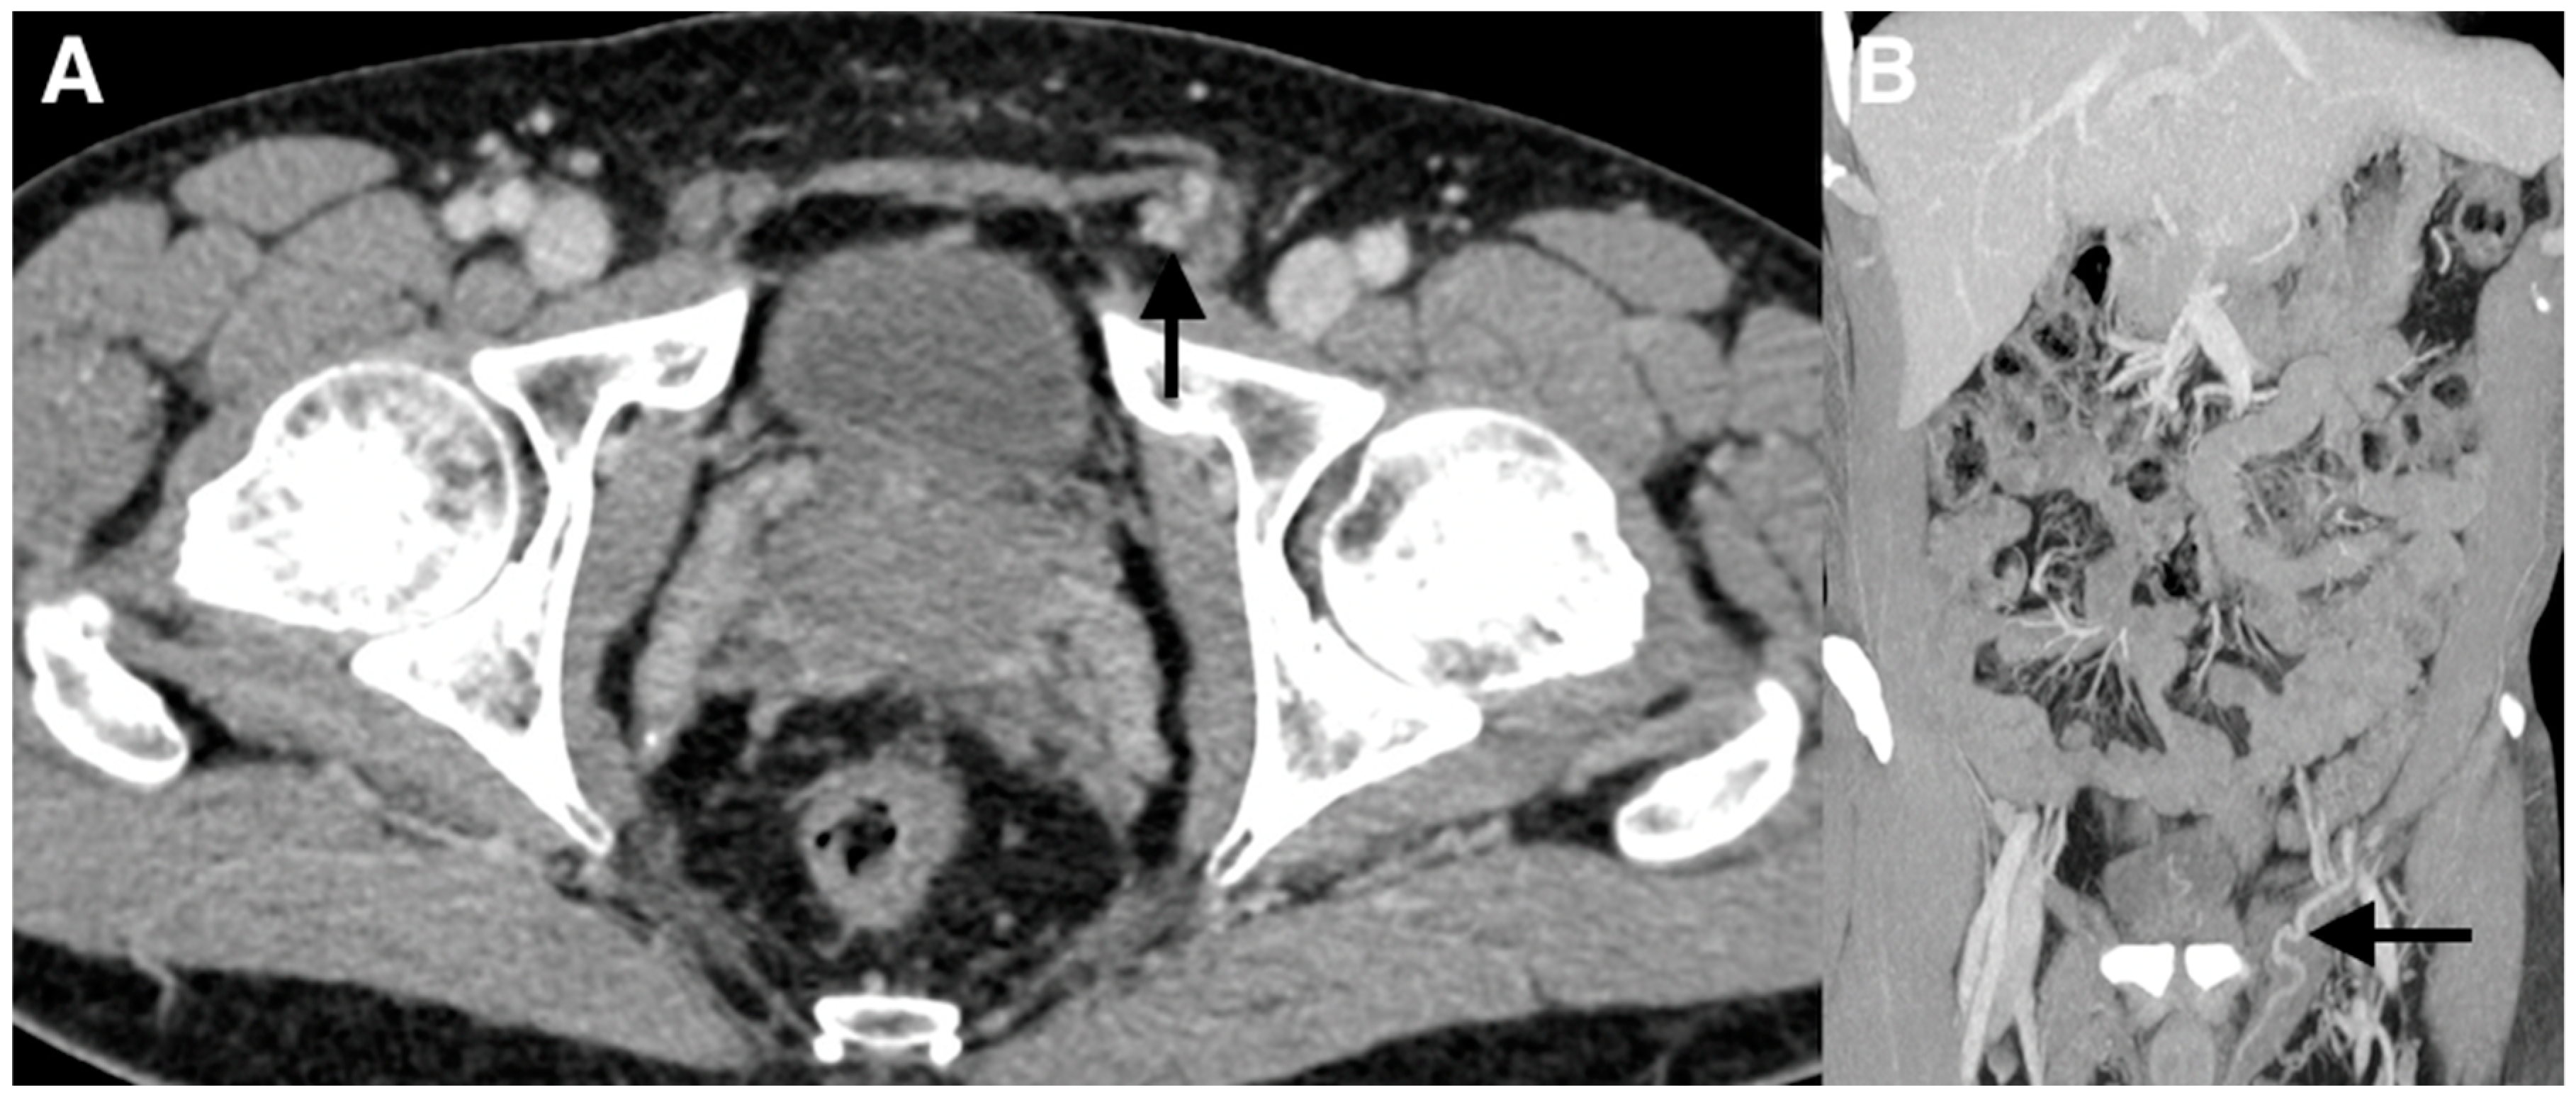

Figure 2. (A,B) Subsequently, a contrast-enhanced computed tomography (CT) imaging study with frontal reconstructions was obtained to evaluate the vasculature. The CT scan did not demonstrate a left testicular vein arising from the left renal vein. The left testicular vein at the level of the inguinal canal was visualized feeding the left-sided varicocele (arrows).